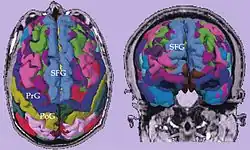

Cortical parcellations derived from SPGR images obtained from a tumor patient.

Cortical parcellations derived from SPGR images obtained from a tumor patient. -